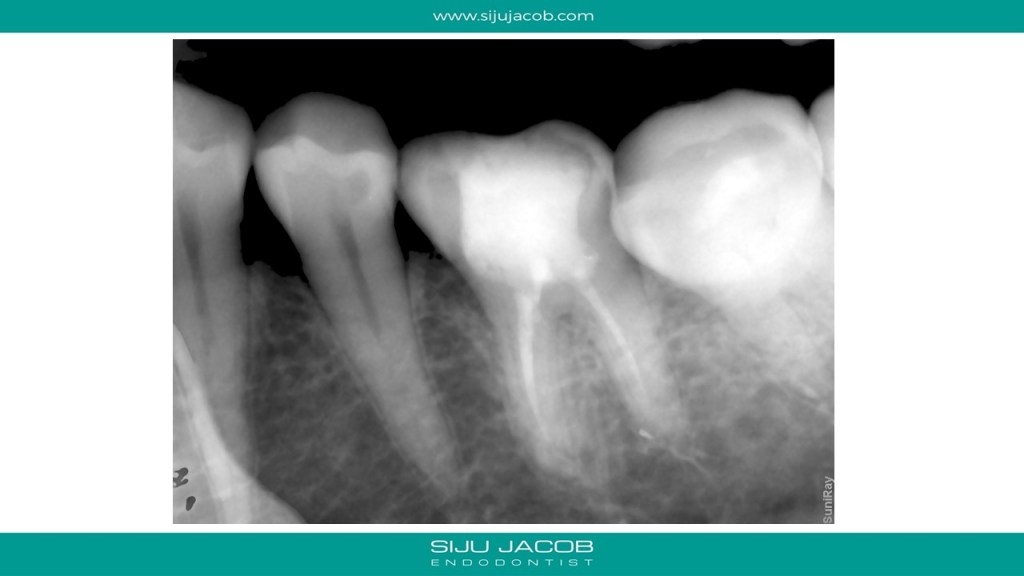

This mandibular molar was previously accessed by an endodontist and then referred. There was a perforation mesially and the canals were located in strange positions. To add to that, the canals were very hard to negotiate and the “feel” was very different to conventional canals. The dentine felt harder than usual. I didn’t want to risk using rotary niti in this case because the feel to rotary too was different when i tried. So, I hand-filed all the canals. Skinny preps in the canal and MTA to seal the Perforation.